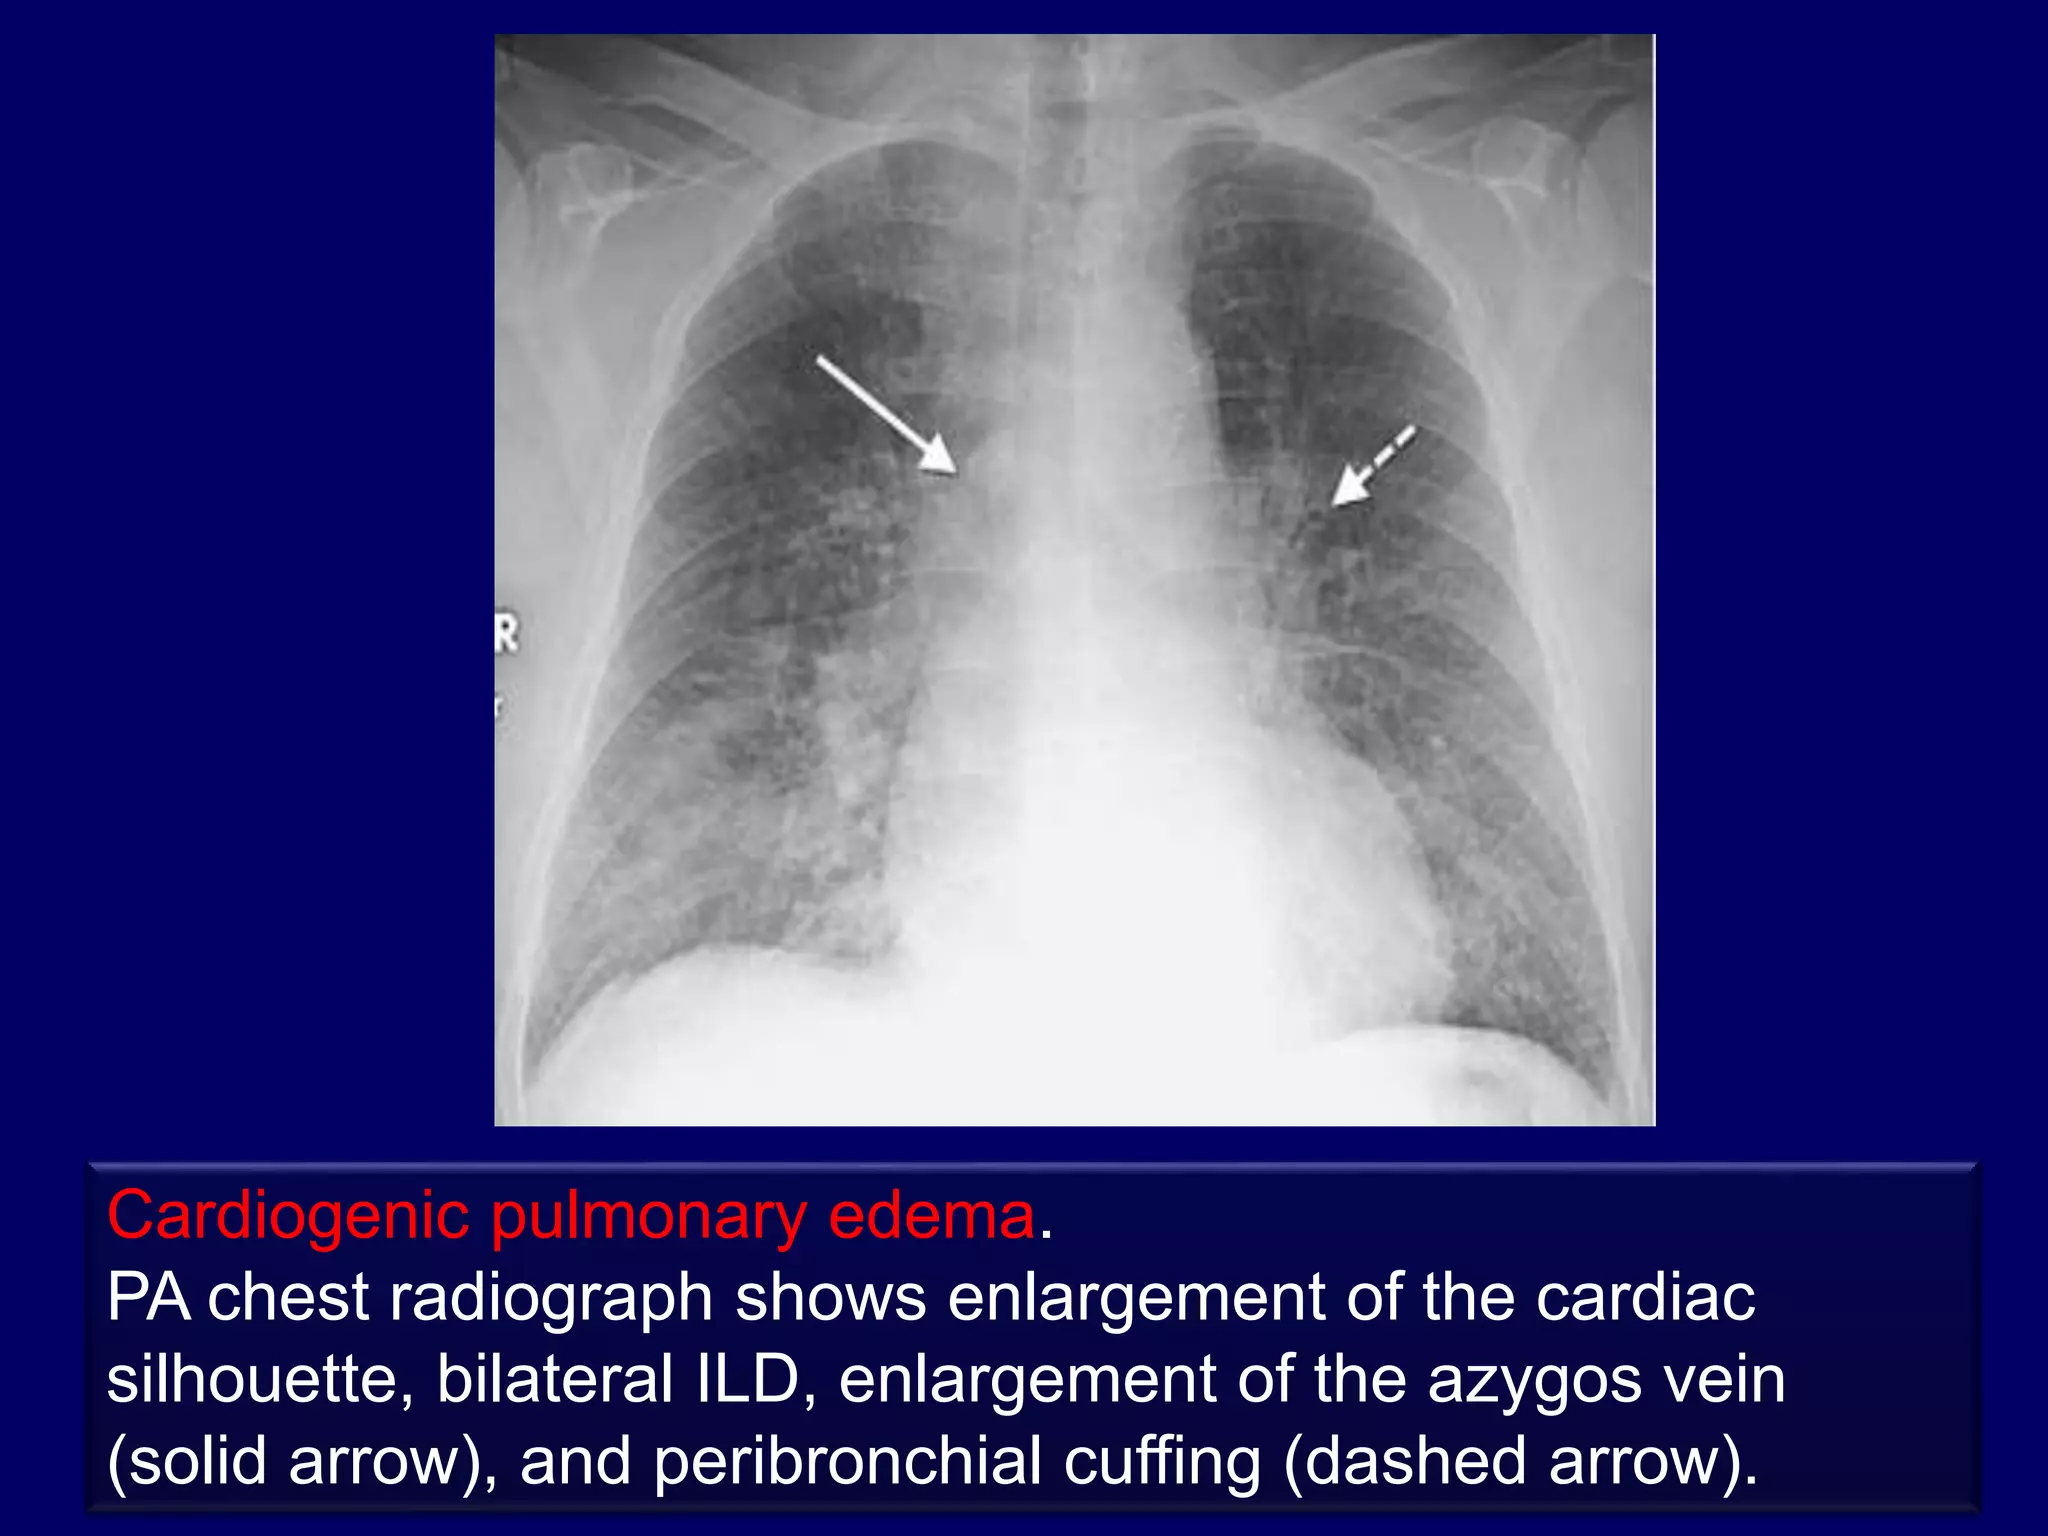

Associated pleural effusion suggests :

1.pulmonary edema

2.lymphangitic carcinomatosis

3.lymphoma

4.collagen vascular disease

Rule no. 6

Cardiogenic pulmonary edema.

PA chest radiograph shows enlargement of the cardiac

silhouette, bilateral ILD, enlargement of the azygos vein

(solid arrow), and peribronchial cuffing (dashed arrow).

Cardiogenic pulmonary edema. PAchest radiograph shows enlargement of the cardiac silhouette, bilateral ILD, enlargement of the azygos vein (solid arrow), and peribronchial cuffing (dashed arrow).